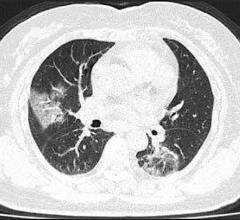

March 31, 2020 — Lung infections generated by the coronavirus can be detected in computed tomography (CT) images.…

March 27, 2020 — Based on recent scientific research, diagnostic X-ray computed tomography (CT) is able to detect COVID…

March 11, 2020 — As COVID-19 spreads in the U.S., there is growing interest in the role and appropriateness of chest…

March 6, 2020 — An article by radiologists from Wuhan, China — published open-access and ahead-of-print in the American…

February 28, 2020 — The first in a series of medical imaging studies on novel coronavirus (COVID-19) was published…

February 26, 2020 — In a study of more than 1,000 patients published in the journal Radiology, chest CT outperformed…